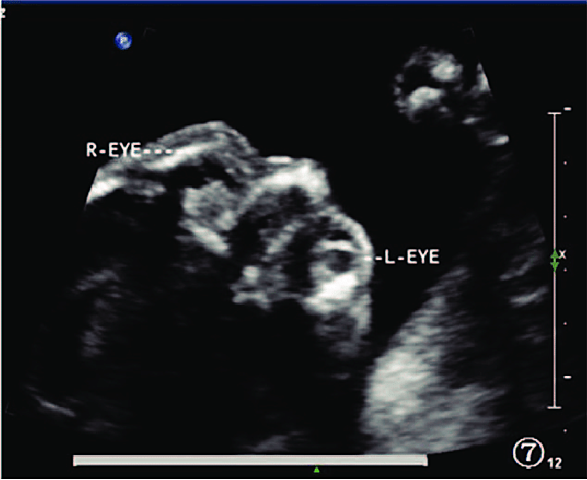

The eyes of a FETUS develop ealry on in the pregnacy but during the FETAL STAGE they become more sensitive to light.

Photo:https://www.researchgate.net/figure/Prenatal-2-dimensional-ultrasound-image-of-both-eyes-the-structures-of-both-eyes-appears_fig6_326789787 -